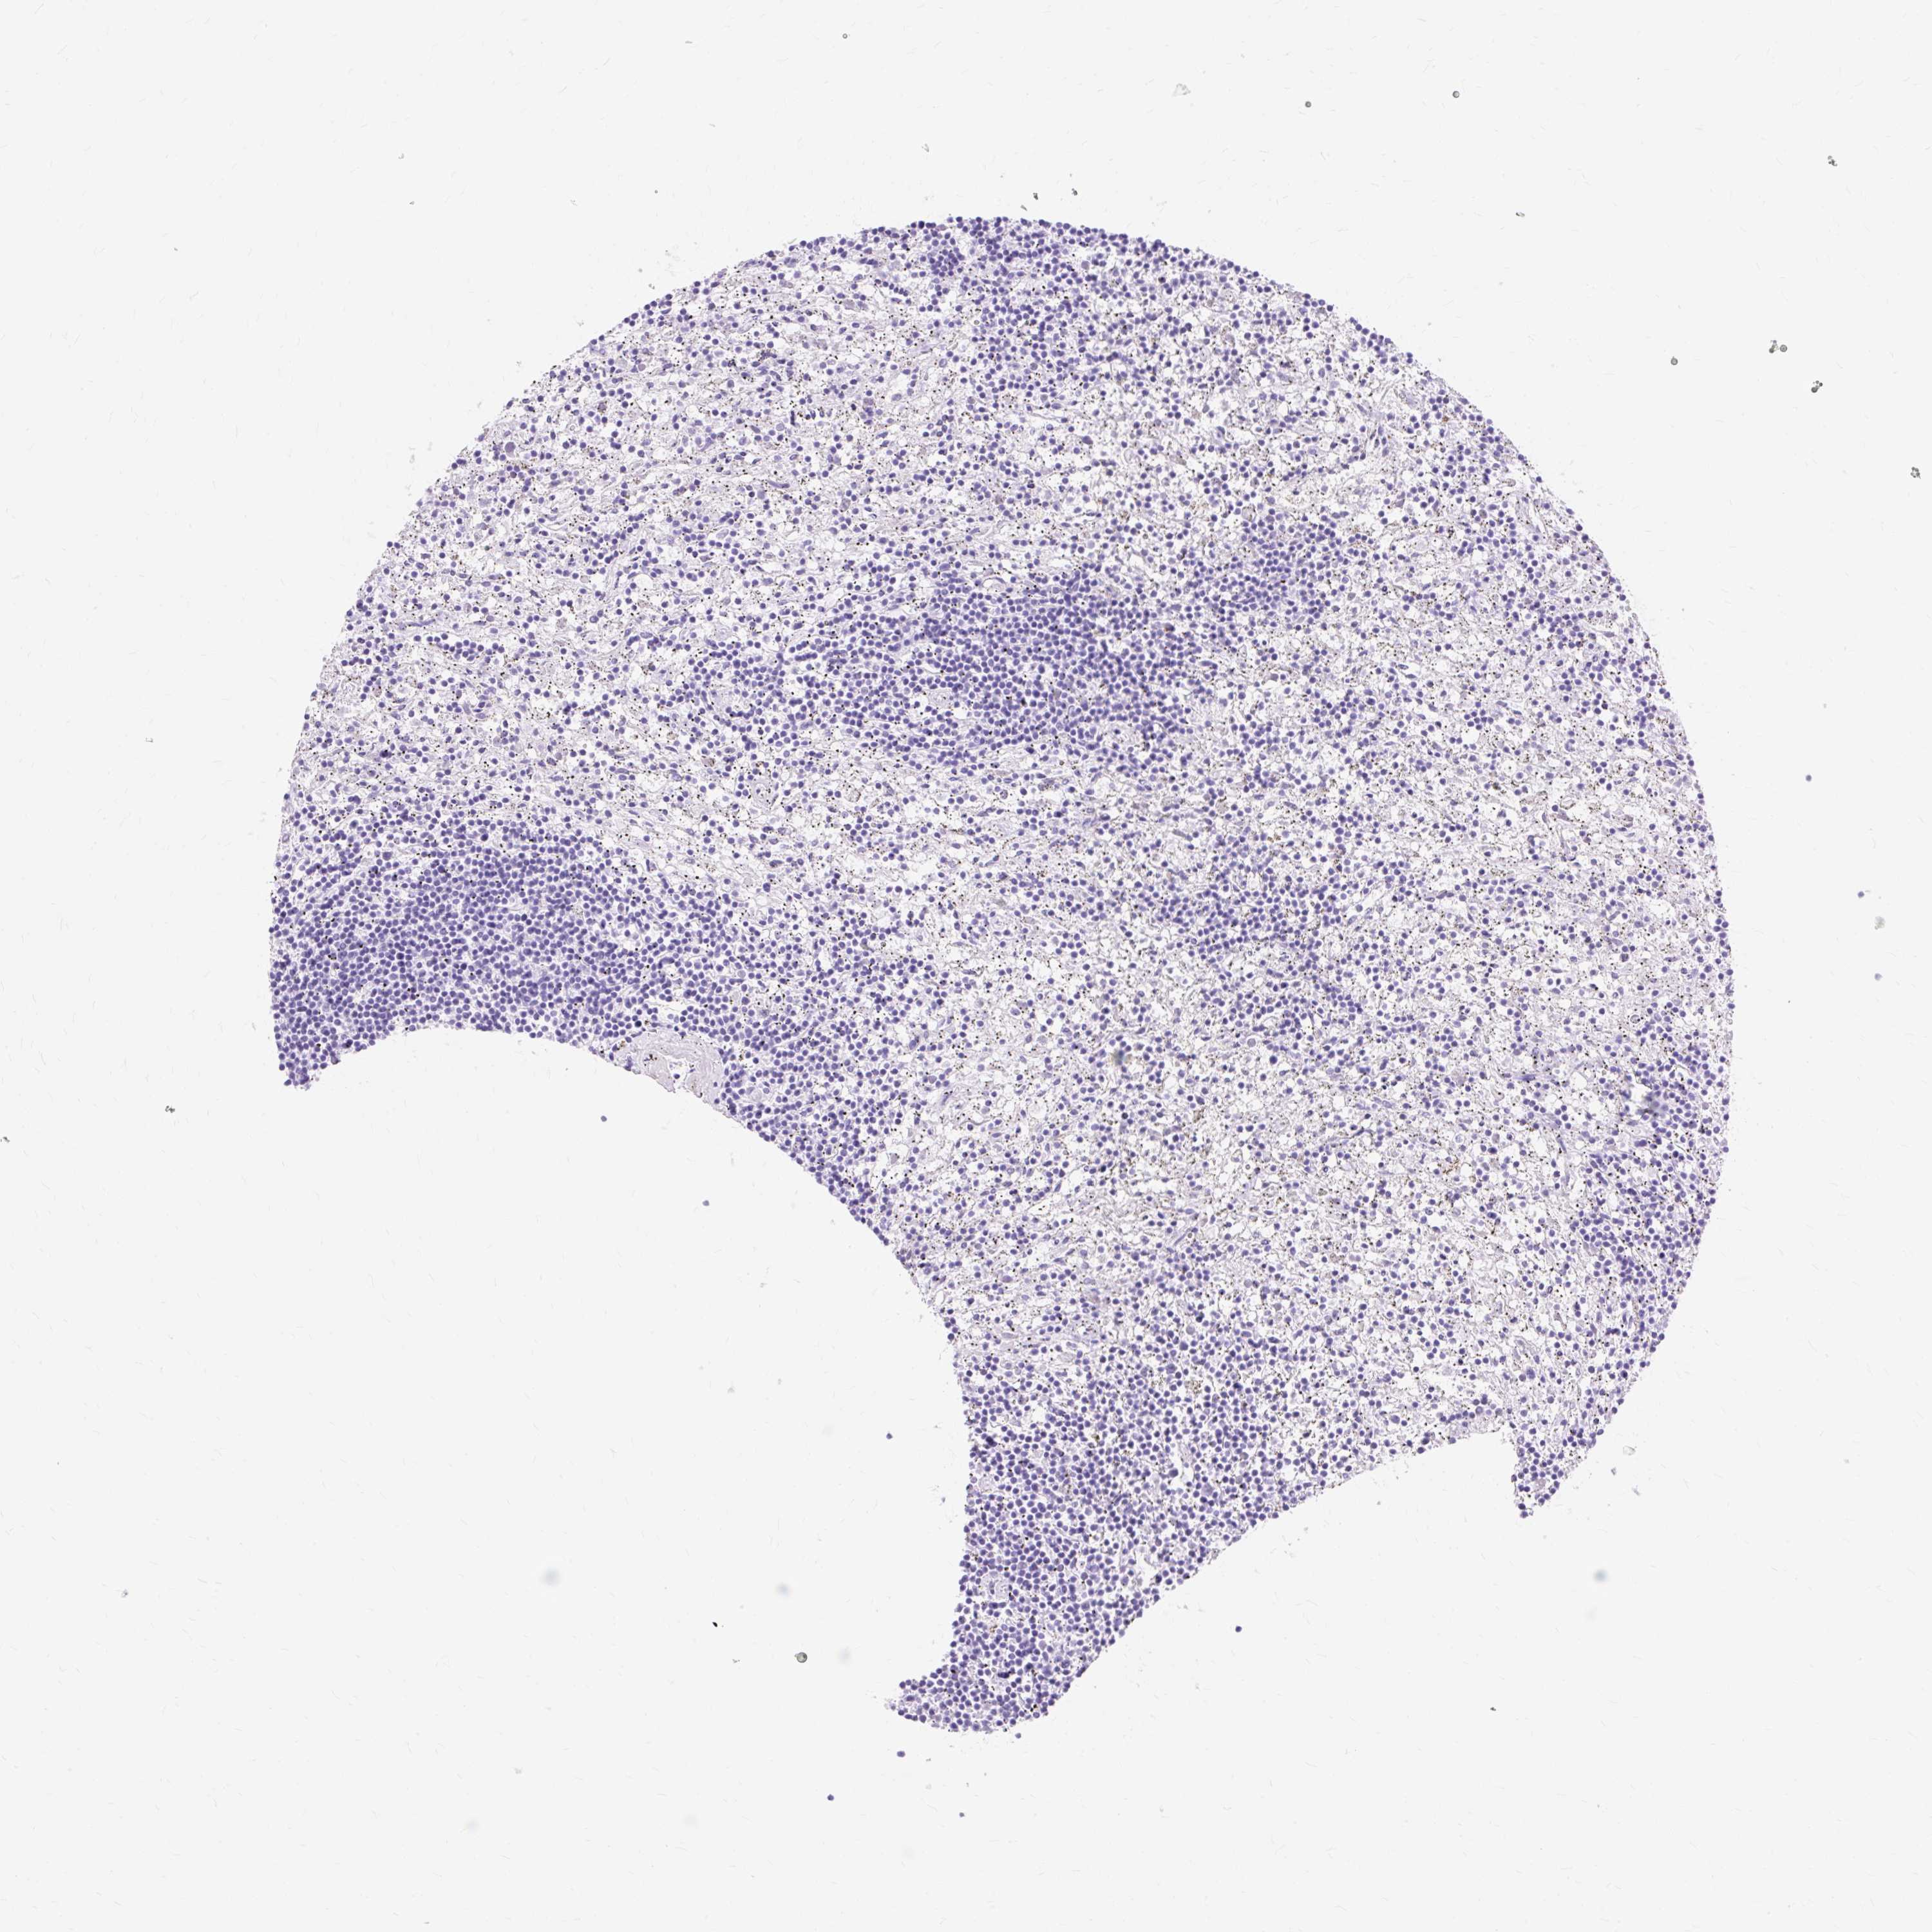

CANCER LYMPHOMA Show tissue menu

LYMPHOMA - Protein expressioni

A mouse-over function shows sample information and annotation data. Click on an image to view it in a full screen mode. Samples can be filtered based on level of antibody staining by selecting one or several of the following categories: high, medium, low and not detected. The assay and annotation is described here.

Each image is clickable and will lead to virtual microscopy that enables deeper exploration of all samples and also displays staining intensity scores, fraction scores and subcellular localization as well as patient and tissue information for each sample.

Antibody CAB002300

Hodgkin's disease, NOS

Malignant lymphoma, non-Hodgkin's type, High grade

Malignant lymphoma, non-Hodgkin's type, Low grade